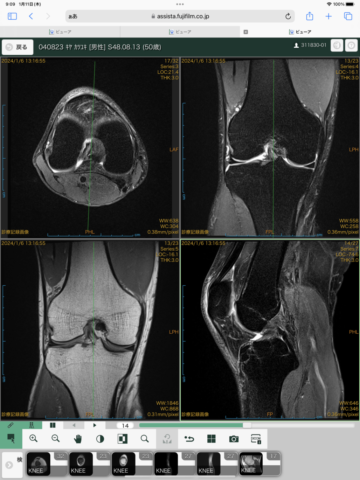

先日、膝のMRIを撮ってきました

当院のDrの勧めでMRIを撮り

痛みの原因について調べることにしました

膝関節の痛みの原因を調べるにはMRIも有効な選択肢です

レントゲンでは分からない、人体や軟骨、軟部組織の状態など調べるのにMRIは最適です

希望日時に大船駅近くの施設へ行きMRIを撮りました

データを頂いたら、その足で当院に行き、膝専門のドクター(北濱Dr)に診察して頂きました

MRIのデータは当院で確認可能です

MRIの結果、靭帯や半月板は問題なし(良かった)

当院でのレントゲン結果から骨そのものは問題なかったのですが…

骨の位置(正常の範囲からのずれ)から、

今後起こるであろう痛みや使いすぎての筋肉、動きのくせなどが分かりました